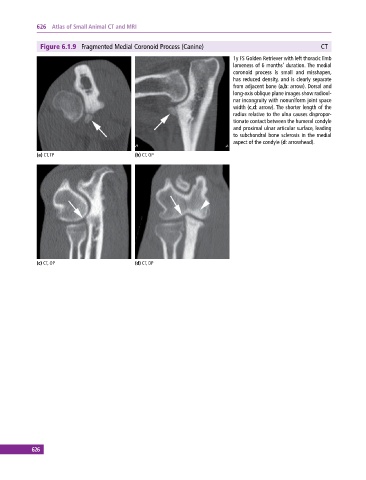

Figure 6.1.9 Fragmented Medial Coronoid Process (Canine) CT

1y FS Golden Retriever with left thoracic limb

lameness of 6 months’ duration. The medial

coronoid process is small and misshapen,

has reduced density, and is clearly separate

from adjacent bone (a,b: arrow). Dorsal and

long‐axis oblique plane images show radioul

nar incongruity with nonuniform joint space

width (c,d: arrow). The shorter length of the

radius relative to the ulna causes dispropor

tionate contact between the humeral condyle

and proximal ulnar articular surface, leading

to subchondral bone sclerosis in the medial

aspect of the condyle (d: arrowhead).

(a) CT, TP (b) CT, OP

(c) CT, OP (d) CT, DP